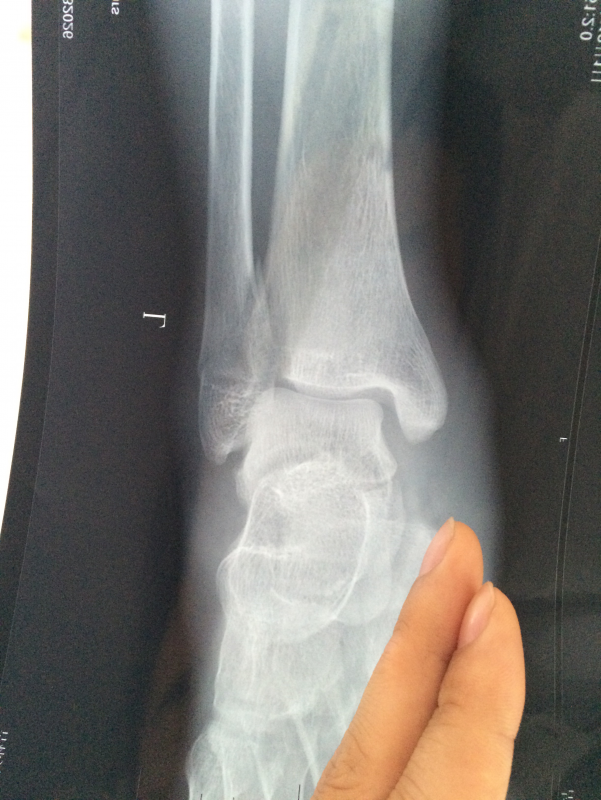

左脚踝腓骨骨折 已有10人参与

需要打钢板吗? 发自小木虫IOS客户端 |